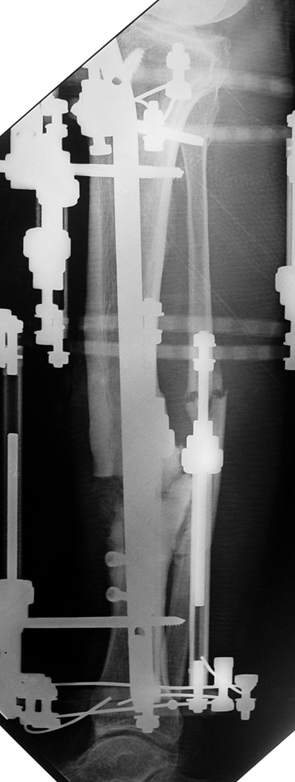

Case 2